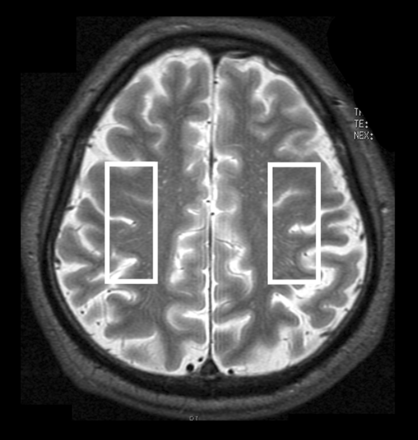

A 3T scanner (Signa Excite HD; GE Healthcare) with a “birdcage” quadrature head coil was used for this study. First, all subjects underwent axial T2-weighted imaging. In the T2-weighted images for each subject, 1 section through the upper gray matter above the centrum semiovale was selected, and a single-voxel region of interest was manually and symmetrically placed in the bilateral cerebral hemispheres so that the proportion of the cortical gray matter and CSF occupying the region of interest was as high and as low as possible, respectively (Fig 1). Voxel size was 17 × 50 × 15 mm3. Next, acquisition of proton MR spectroscopy was performed by using point-resolved spectroscopy with the following parameters: TR, 2000 ms; TE, 144 ms; data size, 4 K points; spectral width, 5000 Hz; 96 acquisitions (3.9 minutes). An area under each peak of 3 main metabolites was automatically obtained on the MR imaging console: choline-containing compounds at 3.2 ppm, total creatine at 3.0 ppm, and NAA at 2.0 ppm. Area ratios for NAA and Cho peaks were expressed as the relative ratio to Cr in each spectrum.

Regions of interest placed on 1 section through the upper gray matter above the centrum semiovale in an axial T2-weighted MR image to obtain MR spectroscopy.